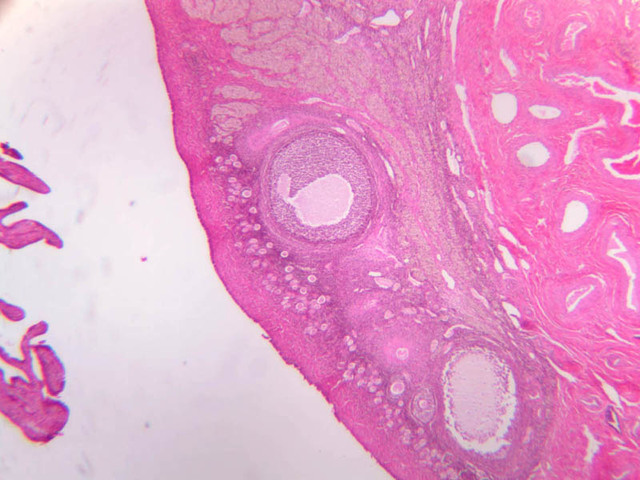

Uterine Cervix

The endometrium of the cervical canal does not slough during the menstrual phase. The glands in this region are relatively large and extensively branched. They are lined by a tall simple columnar epithelium very active in the secretion of mucus. Occasionally these glands become blocked forming Nabothian cysts. The transition of the epithelium of the cervix to that of the vagina is abrupt and is in the region of the external os. At this point, the cervical simple columnar is replaced by the vaginal stratified squamous epithelium (slide B-98 [2.5x-labeled, 10x, 20x, 40x] [2.5x, 10x, 20x, 40x]). This is an area which is commonly inflamed as well as a primary location of cervical cancer.

Vagina

The mucosa of the vaginal wall is lined by non-keratinized stratified squamous epithelium which rests on a lamina propria. The epithelium is indented from beneath by connective tissue papillae. Occasionally aggregations of lymphocytes may be seen within the lamina propria (slide B-98 [2.5x-labeled, 10x, 20x, 40x] [2.5x, 10x, 20x, 40x] [1x, 1x, 1x, 1x, 1x]). The muscularis is said to consist of a poorly defined inner circular and outer longitudinal layer of smooth muscle. An adventitia of fibrous tissue forms the outer most layer of the vaginal wall. Although there is a rather rich vascular plexus in the lamina propria, no glands are present at any location in the vaginal wall.